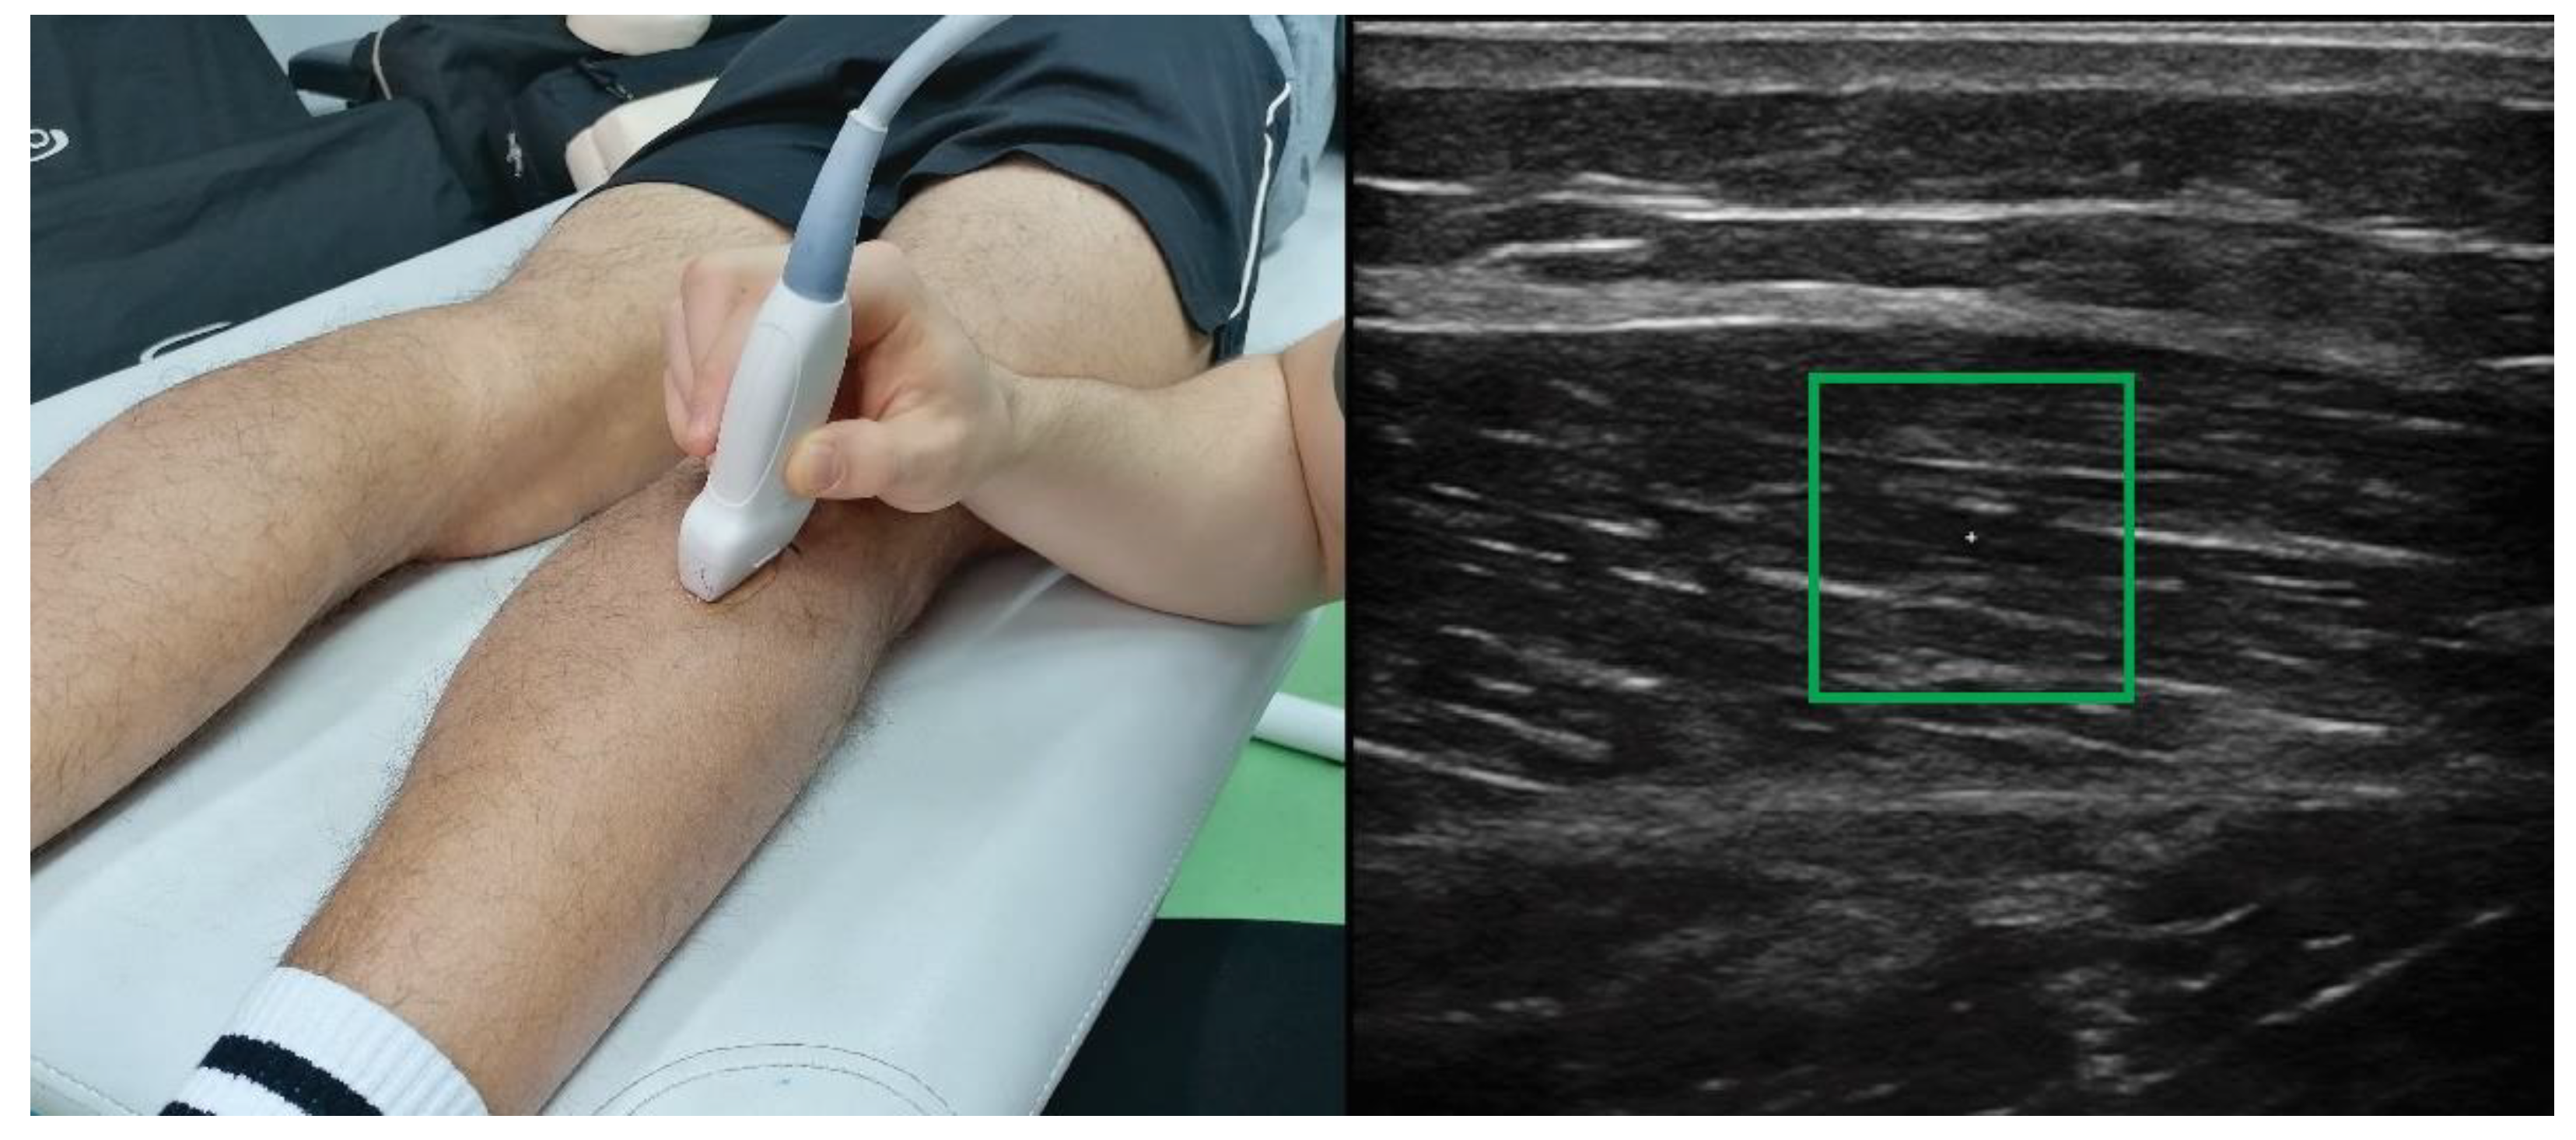

Using Shear-Wave Elastography to Assess Exercise-Induced Muscle Damage: A Review

2. Changes in Shear Modulus after Damaging Exercise